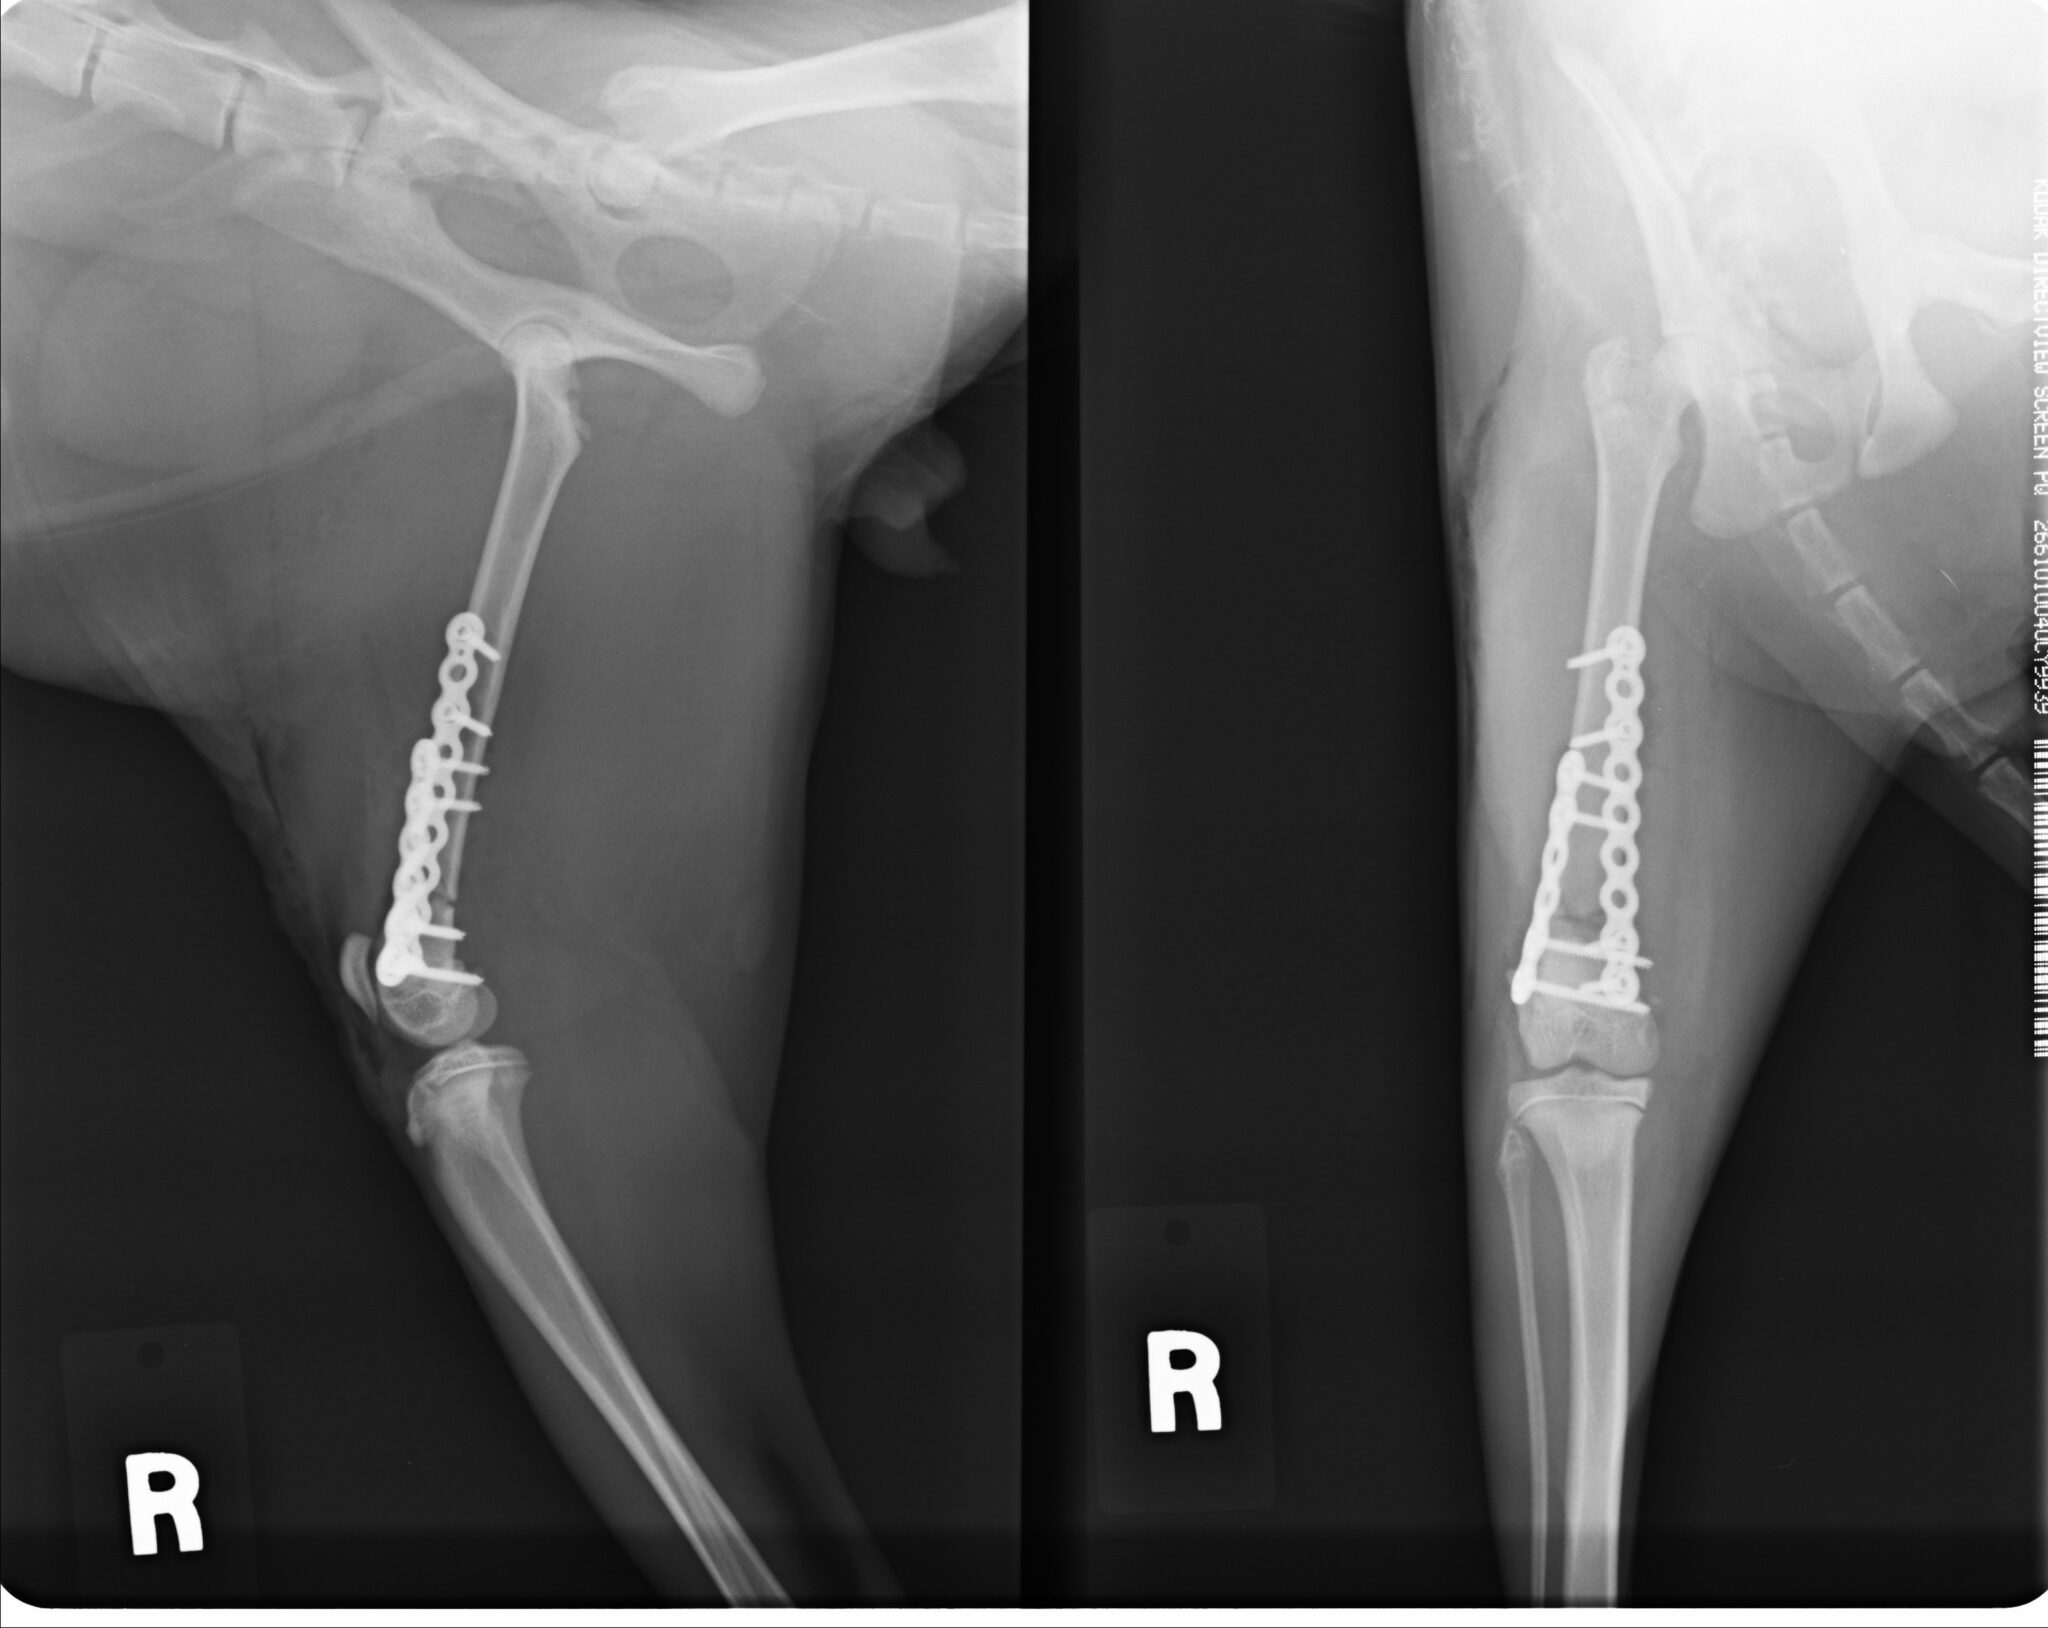

ダブルプレートによる強固な内固定ではピンニングと比べると、早期に歩行が可能になります

骨切りを行う前にインプラントの適応など入念な手術計画が必要です

TPLOをメインの手術手技として取り組んでいます。